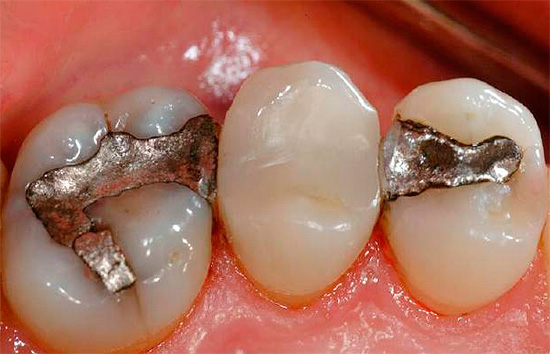

- Amálgamas. Infelizmente para os dentistas, esse material é cada vez menos utilizado devido à complexidade da organização da mistura do material. Esses são os recheios mais duráveis que são misturados ao mercúrio e, portanto, exigem a criação de condições para a proteção do pessoal.

Além do tratamento com técnicas tradicionais de preenchimento, também são utilizados os métodos protéticos das cavidades com abas e coroas. Uma aba é, de fato, um enchimento artificial feito de metal ou cerâmica, feito por um técnico de prótese dentária, e o dentista ortopédico fixa cimento ou adesivos especiais em uma cavidade cariada preparada e limpa.

A conveniência é que a aba substitua cavidades grandes por mensagens com a parte subgengival, e os riscos de fixação são mínimos. Como a aba possui um toco - “cauda”, que é fixado na raiz do dente, ele permanece cimentado de maneira confiável e desempenha suas funções na íntegra.

Uma coroa é uma tampa artificial feita de metal ou uma combinação de metal e cerâmica, que é firmemente fixada ao dente e cobre todas as suas superfícies dos efeitos da infecção da cavidade oral.

A figura abaixo mostra um exemplo de restauração de um dente cariado usando a aba e a coroa:

Uma inserção ou coroa posicionada corretamente fornece excelente proteção do dente contra possíveis complicações da cárie radicular: fratura, fratura da coroa, “cárie”, vários distúrbios gengivais. No entanto, vale lembrar que antes de colocar a coroa, o dente é preenchido de acordo com a tecnologia usual ou a guia é fixada nele e, em seguida, a coroa. Somente isso dá um resultado positivo a longo prazo.